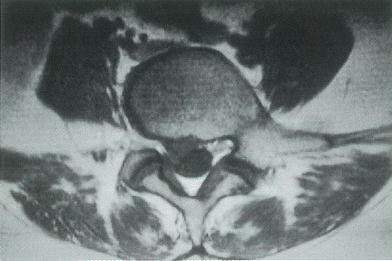

36歳の女性。腰痛と右下肢のしびれとを主訴に来院した。3週前,掃除中に急に強い腰痛が出現し,その後も持続している。1週前から右足部のしびれも自覚している。腰椎には前屈制限があり,Lasegue徴候は右下肢で陽性である。膝蓋腱反射とアキレス腱反射とに異常を認めない。徒手筋力テストで右長母趾伸筋と右長趾伸筋とが4〈good〉,他の筋は5〈very good〉である。右下腿外側と足背とに触覚の低下を認める。腰椎単純MRIのT2強調矢状断像とT1強調横断像とを別に示す。

診断 腰椎椎間板ヘルニア(L4/5レベル,右側)